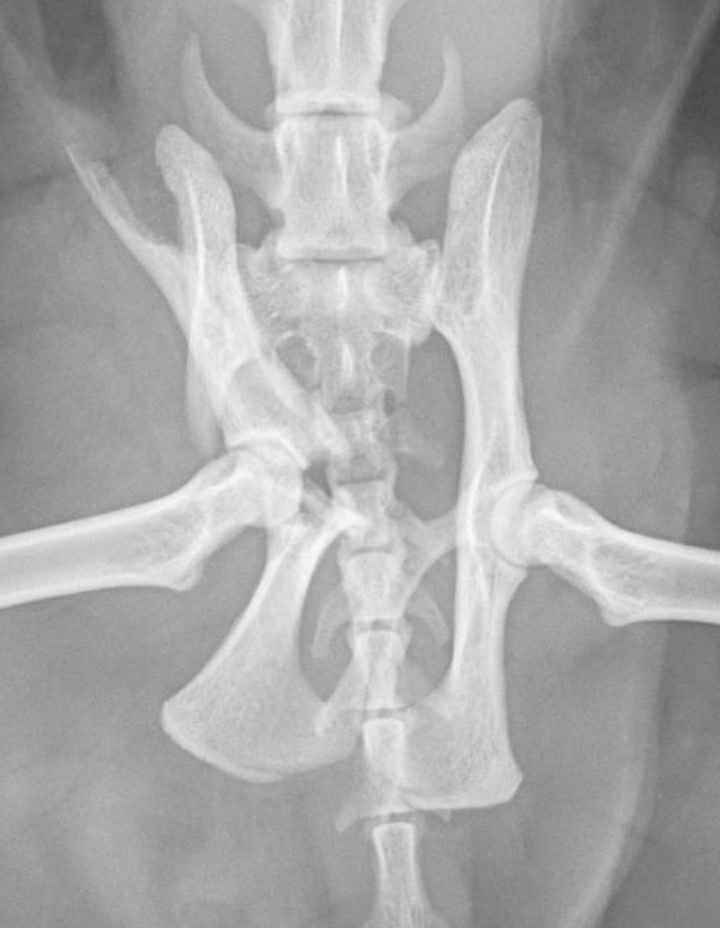

They had stabilised him and taken some x-rays which had revealed that his pelvis was fractured in five places and that his lower jaw was broken. The extent of his injuries meant that he needed urgent specialist care. I said to the vet to do whatever she needed to do to save my boy.

Monday was a long day. I spoke to vet who was going to operate first thing on Monday, and she explained the surgical plan for the day. She planned to put a screw in one side to pin the pelvis at that side to Ragnar’s sacrum. At the other side where the damage was worse, she proposed to plate and pin the top part of his pelvis but as the socket for his hip joint had been destroyed, she would also need to remove the head of his femur to allow the leg to sit in the correct position and give him the best chance of good use of it. The vet estimated that it would take her five hours in theatre.